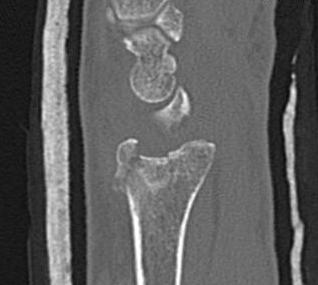

Distal Radius Fracture Articular Step Coronal CTDistal Radius Fracture Articular Step Sagittal CT

Articular incongruency > 2 mm

Distal Radius Fracture DRUJ incongruentDRUJ FractureDRUJ Fracture CT

Sigmoid notch disruption and DRUJ instability